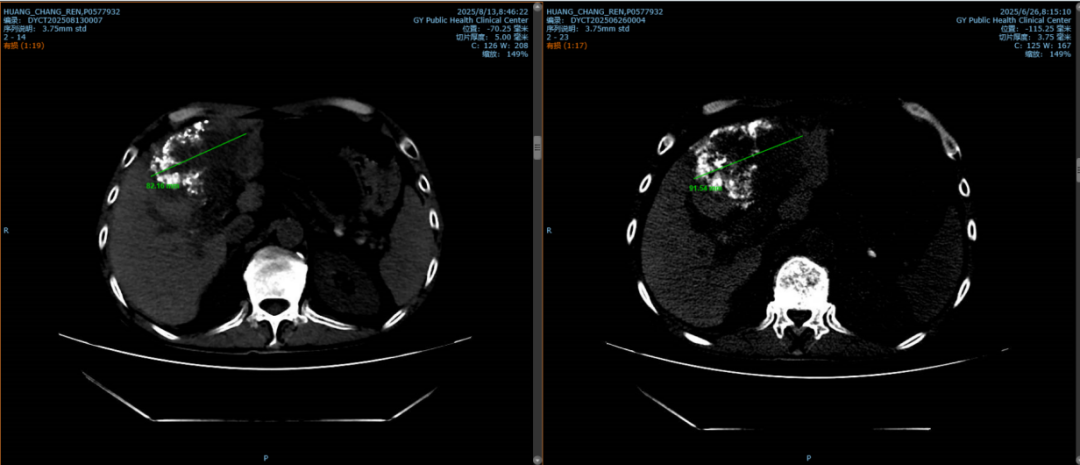

經(jīng)多學(xué)科會(huì)診后,患者于2025-08-06接受HAIC治療,術(shù)中術(shù)后無(wú)特殊不適。復(fù)查結(jié)果令人振奮:影像顯示病灶明顯縮?。ㄆ骄睆綔p少約1cm),甲胎蛋白水平顯著下降(圖5)。

圖1:右側(cè)為第一次TACE術(shù)后病灶直徑約6cm,左側(cè)為此次HAIC術(shù)后病灶縮小約1cm。

圖2:患者病灶最大層面,右側(cè)為第一次TACE術(shù)后病灶直徑約9cm,左側(cè)為此次HAIC術(shù)后病灶縮小至8cm。